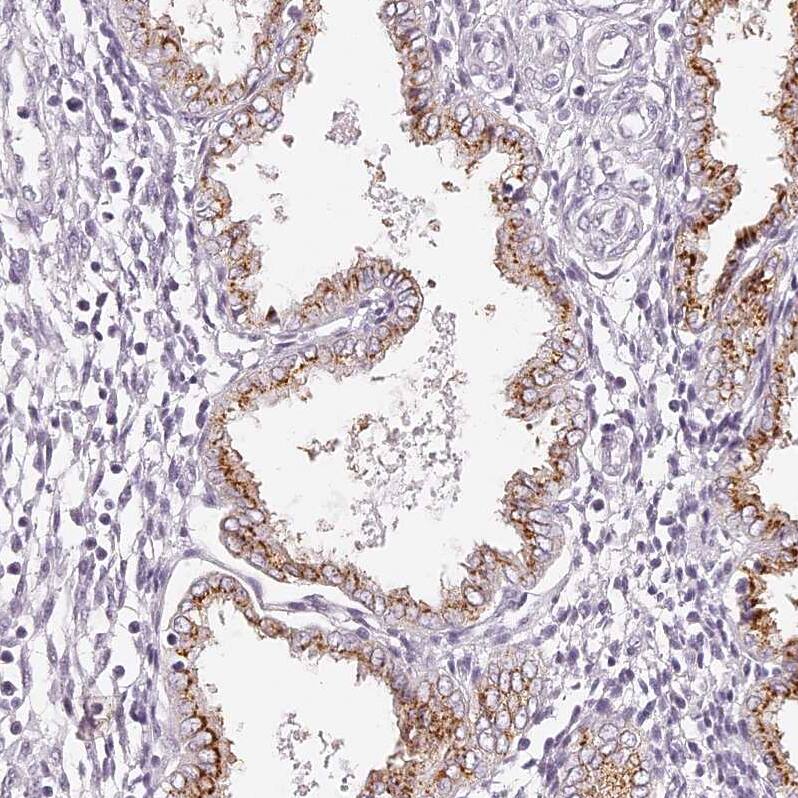

Staining of human endometrium).

Staining of human endometrium shows strong cytoplasm granular positivity in glandular cells.